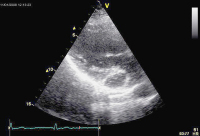

Echokardiographie aktuell: Tubuläre Struktur im Bereich des Sulcus atrioventricularis links bei 2 Patienten

Journal für Kardiologie - Austrian Journal of Cardiology 2009; 16 (1-2): 46-47 Volltext (PDF) Abbildungen mit Filmsequenzen